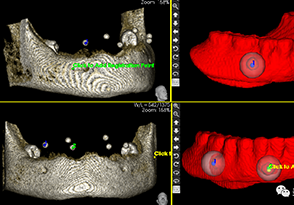

A.将CBCT数据导入软件中

B.绘制下颌神经管

C.添加模型数据

D.图像拟合

F.选择牙位添加种植体

G.选择合适的导环全程或者定位完成植体设计